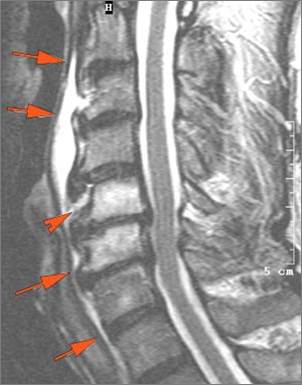

Prevertebral and Epidural Spaces

There is edema/abscess within in the prevertebral or paravertebral spaces. [Yes/No]

There is edema/abscess within in the epidural space. [Yes/No]

There is erosive process involving the disc spaces or other components of the spine. [Yes/No]

Prevertebral abscess, discitis and/or epidural abscess.